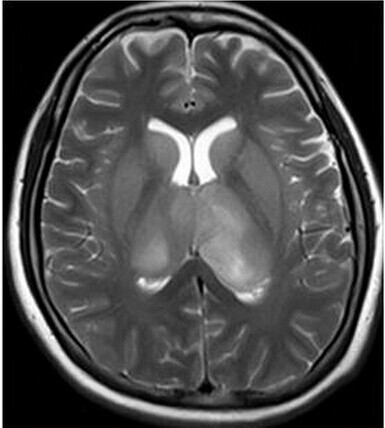

患者:女,23岁,主因嗜睡、言语不利三个月,四肢无力、吞咽障碍3个月入院。

【正确答案】D 大脑胶质瘤病

根据病变同时累及双侧丘脑、基底节,需要与深静脉血栓鉴别。鉴别要点:

(1)CT上可见大脑内静脉高密度影,双侧丘脑低密度影;

(2)MRI上双侧丘脑、基底节、脑干肿胀,不会同时累及双侧颞岛叶;

(3)DWI上早期弥散中度受限,后期恢复;

(4)增强MRI上可见大脑内静脉及直窦的充盈缺损。

大脑胶质瘤病的特征性影像学表现是:

(1)肿瘤常累及2-3个脑叶,白质改变为主,占位效应不明显或轻度占位效应;

(2)病变区大脑结构相对保留;

(3)增强后多无强化。